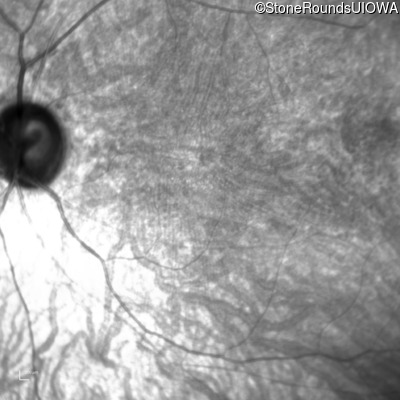

Infrared Fundus Photograph - Right - 10/200 sc

Exemplar